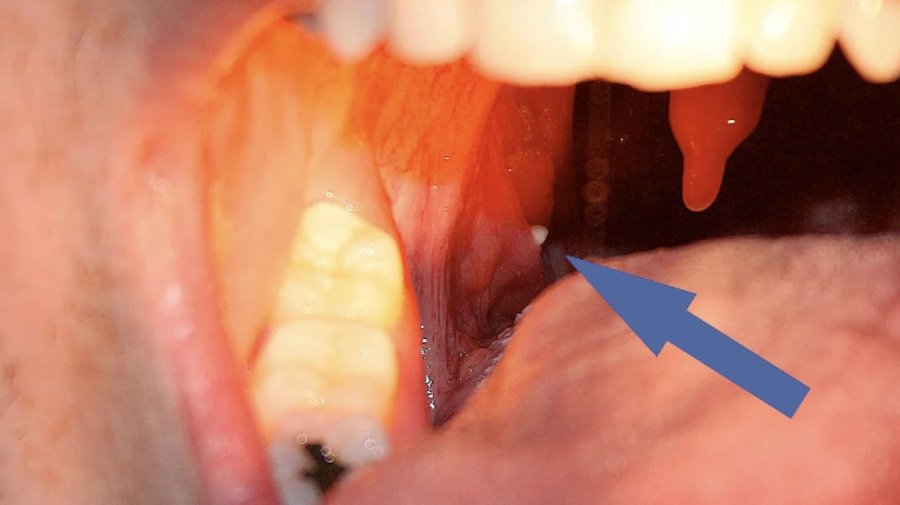

Gurët e bajameve ndodhin kur mbeturinat ngecin në bajame dhe ngurtësohen për shkak të grumbullimit të mineraleve, shpesh duke u shfaqur si njolla të vogla të bardha ose të verdha. Simptomat përfshijnë erën e keqe të gojës, dhimbje të fytit dhe ndonjëherë vështirësi në gëlltitje.

Për gurët e vegjël të bajameve, provoni t’i hiqni ato me kujdes me një shtupë pambuku ose furçë dhëmbësh. Gargara me ujë të kripur (një lugë çaji për filxhan ujë të ngrohtë) gjithashtu mund të ndihmojë në lirimin dhe nxjerrjen e gurëve më të vegjël. Waterpiks mund të synojnë mbeturinat në mënyrë më efektive. Për gurët më të mëdhenj, një mjek mund t’i heqë ato në zyrë, ose për probleme të përsëritura, të marrë në konsideratë kriptolizën me lazer ose, në raste të rënda, një tonsilektomi.